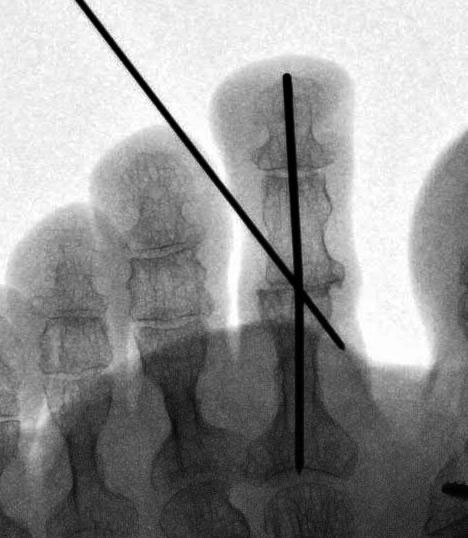

Die vorbereitenden Operationsschritte werden im Abschnitt „PIP-Arthrodese mit K-Draht-Fixierung“ in den Abbildungen 1.1 bis 1.7 beschrieben.

• Eine Röntgenkontrolle wird 6 Wochen postoperativ durchgeführt (Fuß belastet in zwei Ebenen). Besonders geachtet wird auf eine knöcherne Konsolidierung der Arthrodese und auf die Lage eines gegebenenfalls verwendeten intramedullären Implantats.